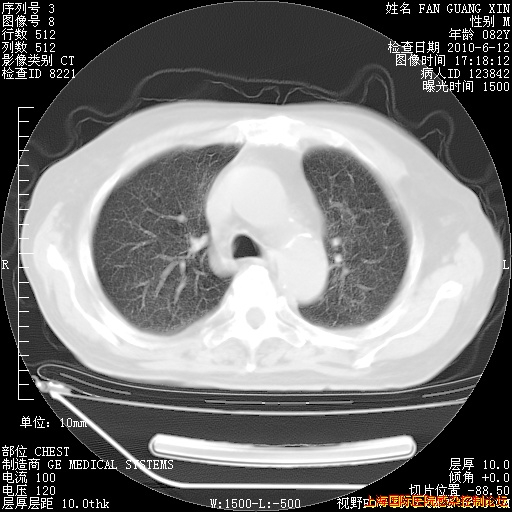

补发6月12日肺部CT肺窗

6月12日肺窗